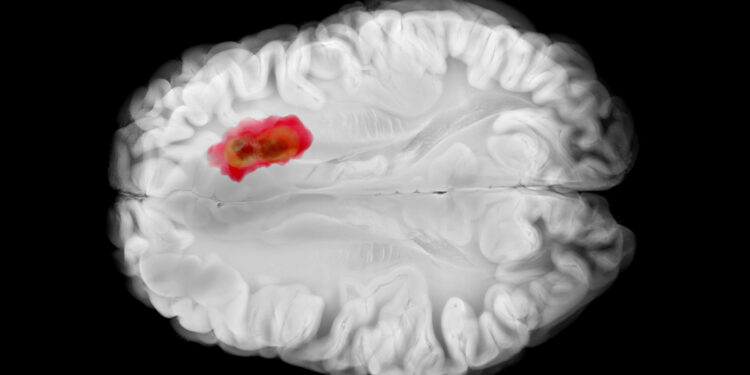

(MedPage Today) — For the second time, glioblastoma has been linked to Alice in Wonderland Syndrome (AIWS), a rare neurological disorder that can cause distorted perceptions like those the fictional character experiences when she falls down a…